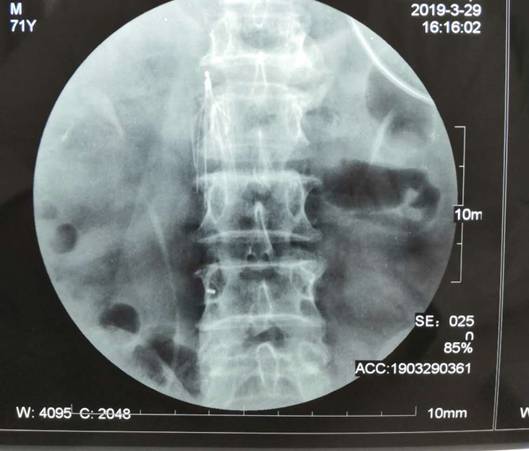

3月29日,东院由血管外科与骨科密切合作,成功实施渭北首例新型可回收下腔静脉滤网置入术。

患者王某因骨折合并双下肢深静脉血栓来东院就诊,骨科宋楹卓主任和本部血管外科杨林副教授会诊后,认为患者深静脉血栓复合较重,随时有发生肺栓塞猝死的危险性,必须抓紧手术。汇报血管外科刘建林主任后,决定对患者先行下腔静脉滤网置入术,预防致死性肺栓塞发生,再进行人工股骨头置换。在完善相关检查后,明确患者具有手术适应症,由杨林副教授手术,宋楹卓主任协助,在局麻下行新型可回收下腔静脉滤网置入术,手术顺利。随后在全麻下行左侧人工股骨头置换术,术后第二天患者便能下地站立。